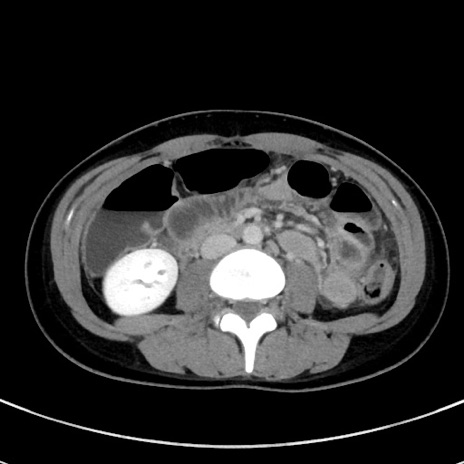

症例17(横断像)

【症例】20歳代女性

【主訴】嘔吐、下腹部痛

【現病歴】昨日夕食後に嘔吐し下腹部痛が出現。本日になっても嘔吐持続し改善しないため来院。

【身体所見】意識清明、BT 37.2℃、BP 108/67mmHg、腹部:平坦、やや硬、下腹部正中から右にかけて圧痛あり、反跳痛軽度あり、tapping pain(+)。

【データ】WBC 13600、CRP 14.94